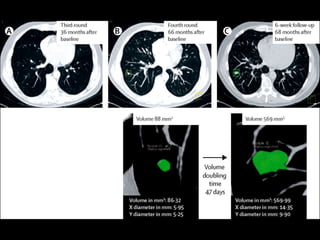

Doubling time

If a lesion doubles in volume

>6 weeks and <16 months,

usually malignant